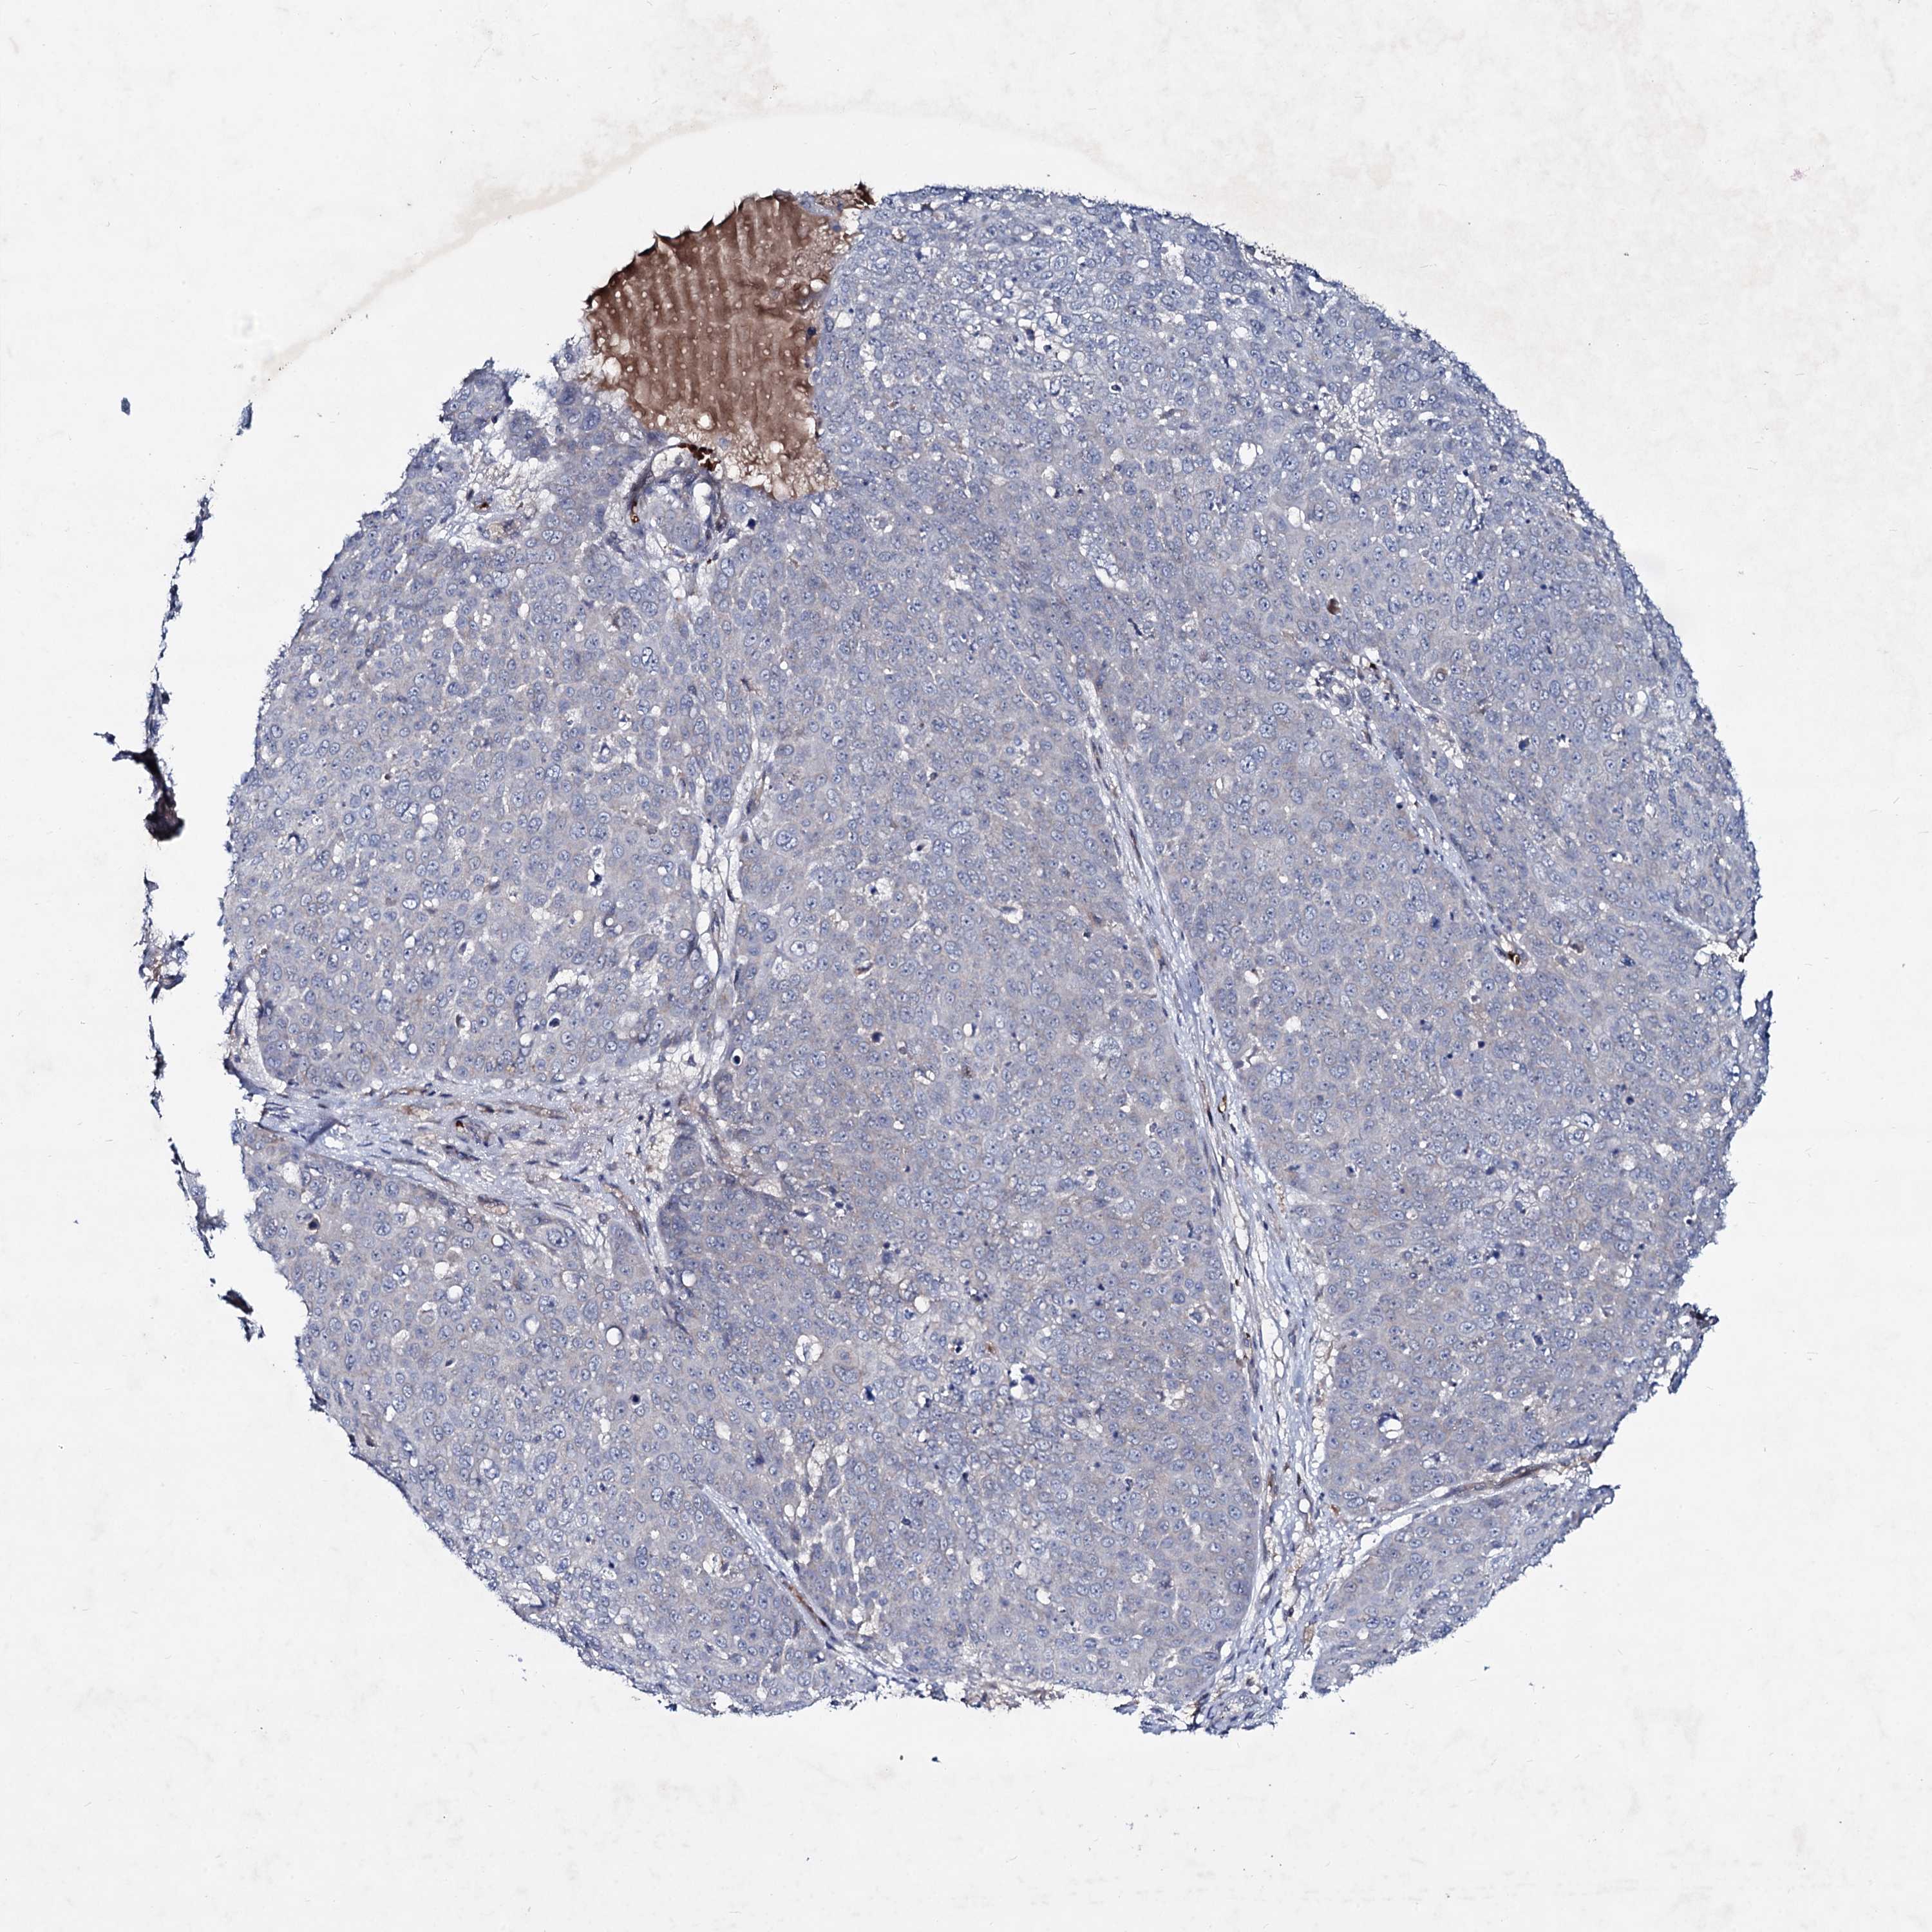

Basal cell and squamous cell cancer

SKIN CANCER - Protein expressioni

A mouse-over function shows sample information and annotation data. Click on an image to view it in a full screen mode. Samples can be filtered based on level of antibody staining by selecting one or several of the following categories: high, medium, low and not detected. The assay and annotation is described here.

Each image is clickable and will lead to virtual microscopy that enables deeper exploration of all samples and also displays staining intensity scores, fraction scores and subcellular localization as well as patient and tissue information for each sample.

Antibody HPA040048

Basal cell carcinoma

Squamous cell carcinoma, NOS

Squamous cell carcinoma, metastatic, NOS